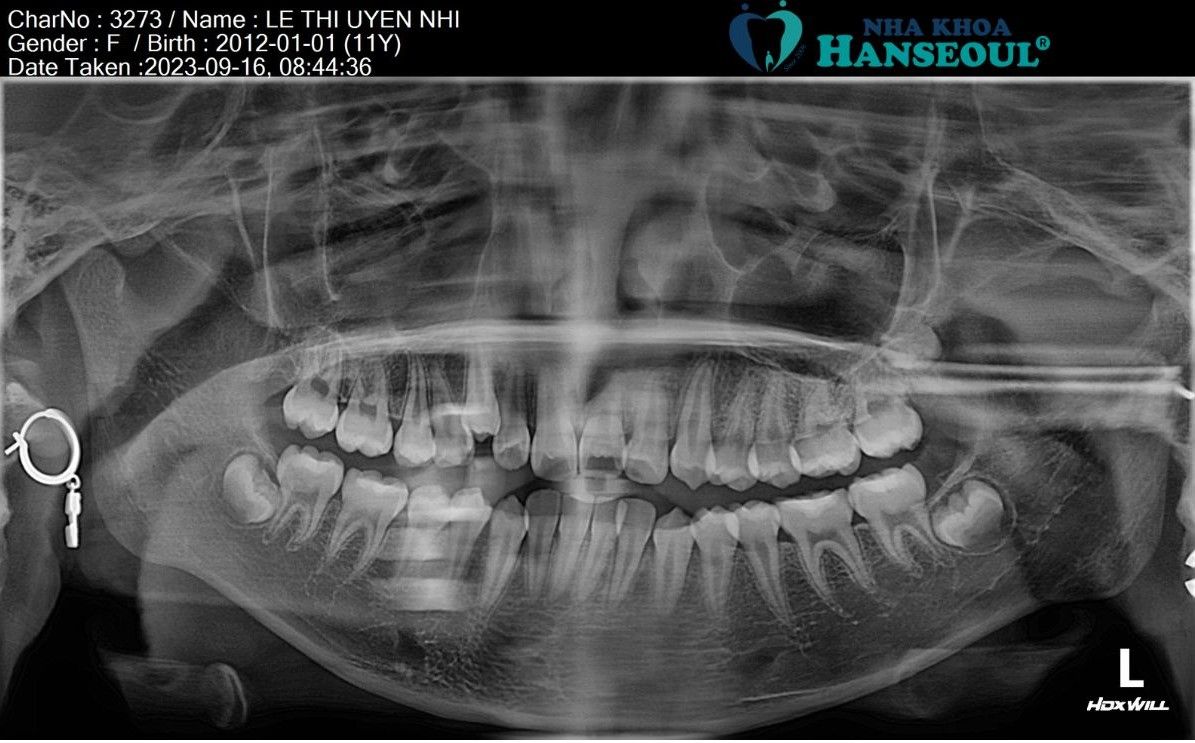

Tình trạng được xác định thông qua:

- Khám lâm sàng (ngoài mặt và trong miệng)

- Phim X-quang toàn cảnh (Panoramic) đánh giá răng vĩnh viễn và cấu trúc xương hàm